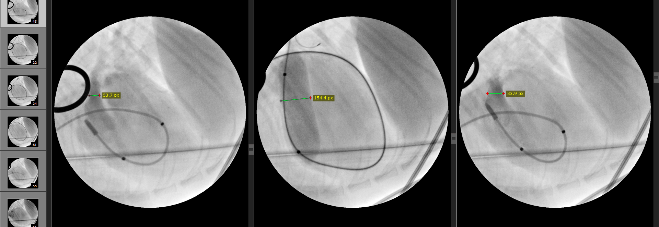

ペースメーカー・リード線心外膜スクリュー留置術

ペースメーカー・リード線心外膜スクリュー留置術としては、一時ペーシングを行い、心外膜にスクリュー留置し、ペーシング試験を行います。